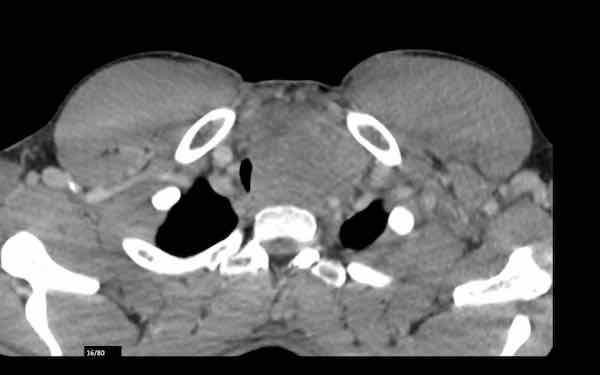

Ung thư tuyến ức

Ca lâm sàng 1

Các hình ảnh này của một bệnh nhân bị ung thư tuyến ức.

Lưu ý hoạt độ phóng xạ không đều ở ngoại vi tổn thương trên PET.

Khối u đã được phẫu thuật cắt bỏ.

Trong quá trình theo dõi, một CT được thực hiện.

Tiếp tục xem CT theo dõi…

Trên CT, phát hiện các cấu trúc tăng tỷ trọng mới trong các đốt sống (mũi tên).

Chúng không có trên CT trước đó.

Nhận định của bạn là gì?

Hãy phân tích hình ảnh trước rồi tiếp tục đọc.

Hình ảnh

Lưu ý sự hiện diện của các tĩnh mạch bàng hệ giãn. Điều này được giải thích bởi thực tế là trong phẫu thuật, tĩnh mạch tay đầu (brachiocephalic vein) bị thắt lại, có thể dẫn đến sự hình thành các tĩnh mạch bàng hệ đáng kể. Các cấu trúc tăng tỷ trọng quan sát thấy trong thân đốt sống không phải là di căn xơ cứng, mà là hậu quả của ứ trệ tĩnh mạch. Những hình ảnh này biểu hiện sự ngấm thuốc do ứ trệ tĩnh mạch, không phải bệnh di căn. Trên CT không tiêm thuốc cản quang, tình trạng tăng tỷ trọng này sẽ không quan sát được.

Tiếp tục xem phim theo dõi muộn hơn…

Trên phim theo dõi muộn hơn, tình trạng ứ trệ tĩnh mạch không còn quan sát thấy nữa.